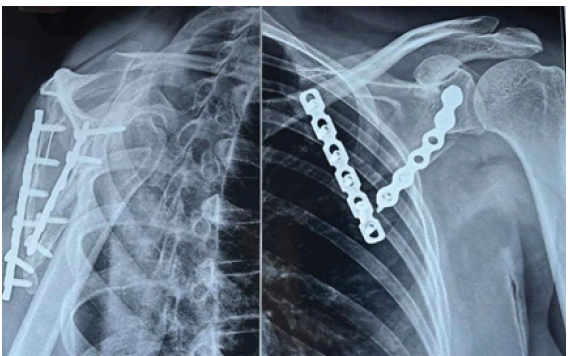

The infraspinatus was gently retracted superomedially and the teres minor inferolaterally, exposing the lateral border and body of the scapula. A separate subperiosteal plane was created beneath the infraspinatus medially, allowing exposure of the vertebral border for plate placement. Broad, gentle retraction minimized muscle strain and preserved perfusion. At the non-union site, fibrous tissue and sclerotic bone were excised until fresh bleeding cancellous bone was encountered. The fragments were mobilized and anatomically reduced. A pointed Verbrugge bone clamp was applied across the fracture – one jaw along the lateral border and the other on the vertebral fragment – providing compression while maintaining alignment. Temporary fixation was confirmed both visually and fluoroscopically. An autologous cancellous bone graft harvested from the ipsilateral iliac crest was packed into the defect. Fixation was achieved using two contoured 3.5-mm reconstruction plates: one along the lateral border to resist bending and shear, and another along the vertebral border to restore the scapular ring and resist torsional forces [10]. Screws were tightened sequentially to maintain compression across the fracture, and fluoroscopy confirmed satisfactory alignment and fixation. After irrigation, hemostasis, and drain placement, the infraspinatus and teres minor were reapproximated with absorbable sutures to restore the posterior envelope. The deltoid fascia was closed anatomically, followed by layered closure of subcutaneous tissue and skin. Postoperatively, the shoulder was immobilized in a sling for 3 weeks. Pendulum exercises were initiated thereafter, progressing to active-assisted and active motion at 6 weeks. At 3 months, radiographs confirmed solid union with resolution of pain (Fig. 3). At 1 year, the patient was pain-free, had full shoulder motion (abduction 170°, external rotation 70°, and internal rotation to the level of T8), and had returned to all pre-injury activities (Fig. 4).

Figure 3: Post-operative radiograph at 3 months showing solid union with dual-plate fixation.